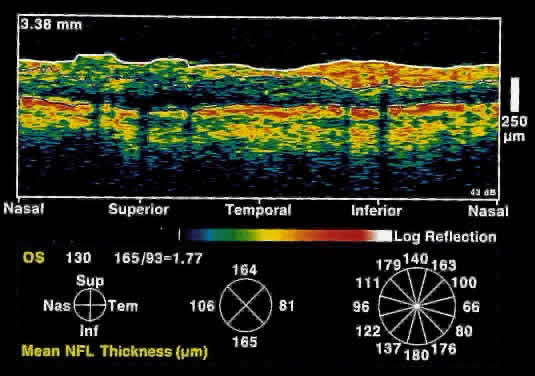

The diagnosis and management of glaucoma remains a difficult clinical problem. Intraocular pressure measurements do not always adequately predict the extent of glaucomatous change. Optic nerve head and gonioscopic evaluation by slit-lamp biomicroscopy is subjective. Visual field loss and optic nerve head cupping are late clinical findings, detected only after up to 50% of retinal nerve fibers have been lost.

OCT, because of its high resolution, is able to detect nerve fiber layer thinning before the onset of visual changes.21 Nerve fiber layer thickness, as measured by OCT, has been shown to correspond to visual function. As expected from the histology of the peripapillary retina, the nerve fiber layer is thickest in the inferior and superior quadrants. The nerve fiber layer has been demonstrated to be significantly thinned in areas corresponding to visual field loss.

Typically, the scans are performed radially around the optic nerve for 360° using two radii of curvature (2.25 and 3.37 mm), and the nerve fiber layer thickness is plotted schematically (Fig. 16). Normal nerve fiber layer thickness is a mean of 148.6 microns for superior nerve fibers, 143.5 microns for inferior nerve fibers, 66.9 microns for temporal nerve fibers, and 117.2 for nasal nerve fibers. The direct measurement of the nerve fiber layer thickness by OCT is an objective assessment of glaucomatous progression. OCT shows promise in the early diagnosis of glaucoma before visual field defects, optic nerve head changes, and ophthalmoscopically visible nerve fiber layer loss are evident.

Fig. 16. Circular OCT image of a normal eye taken in cylindrical section around the optic nerve head. Note the thicker nerve fiber layer superiorly and inferiorly.